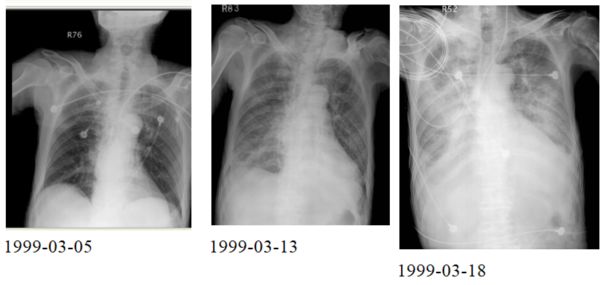

3. 病人18歲女計程車無線呼叫員, 到院主訴有五天的間 歇性燒熱及寒顫(chillness), 並合併頭痛、雙眼後疼痛及全身肌疼, 經初步診斷腦膜炎, 病人拒絕腰椎穿刺檢查, 乃試用抗生素後回家療養。 唯症狀仍舊, 尚有噁心、嘔吐, 並先後在左大拇指及右小趾出現疼痛紅斑(如圖A及B所示)。既往病史有二尖瓣膜脫垂及閉鎖不全。理學所見身高:162cm;體重:45Kg;BP:105/67mmgHg;T/P/R: 39.8C/155/18。未見Meningeal signs. 頸部末見異常, 心尖在left 5th ICS, mid-clavicular line, 有Grade III/VI Pansystolic murmur. S1及S2正常。胸、腹都無不正常。實驗室檢查: WBC:4.39x k/uL,有left shifting;RBC:5.12 x M/uL;Hb:11.0 g/dL;Platelets:130 x K/uL;其血液細菌培養結果如與胸部X光詳見附圖C、D。心電圖如附。本病人經過下列臨床處置